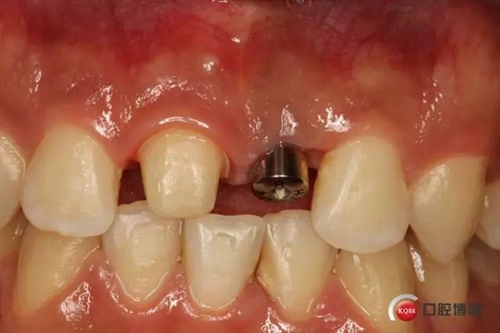

種植后修復(fù),我們要把握每一個(gè)細(xì)節(jié),比色,轉(zhuǎn)移桿的就位,我們必須把臨床做好,技工師傅才會(huì)給我們做出好的修復(fù)體,減少一些不必要的失誤,首先術(shù)前的檢查是必要一步 ,再是器械的準(zhǔn)備使我們臨床操作有條不紊,術(shù)前拍照,o-bite取咬合記錄,消毒修復(fù)術(shù)區(qū),旋出愈合基臺(tái),生理鹽水沖洗袖口,拍照袖口,安放合適轉(zhuǎn)移桿,拍X線見轉(zhuǎn)移桿就為良好,硅橡膠取模,術(shù)后旋回愈合基臺(tái),拍照比色。